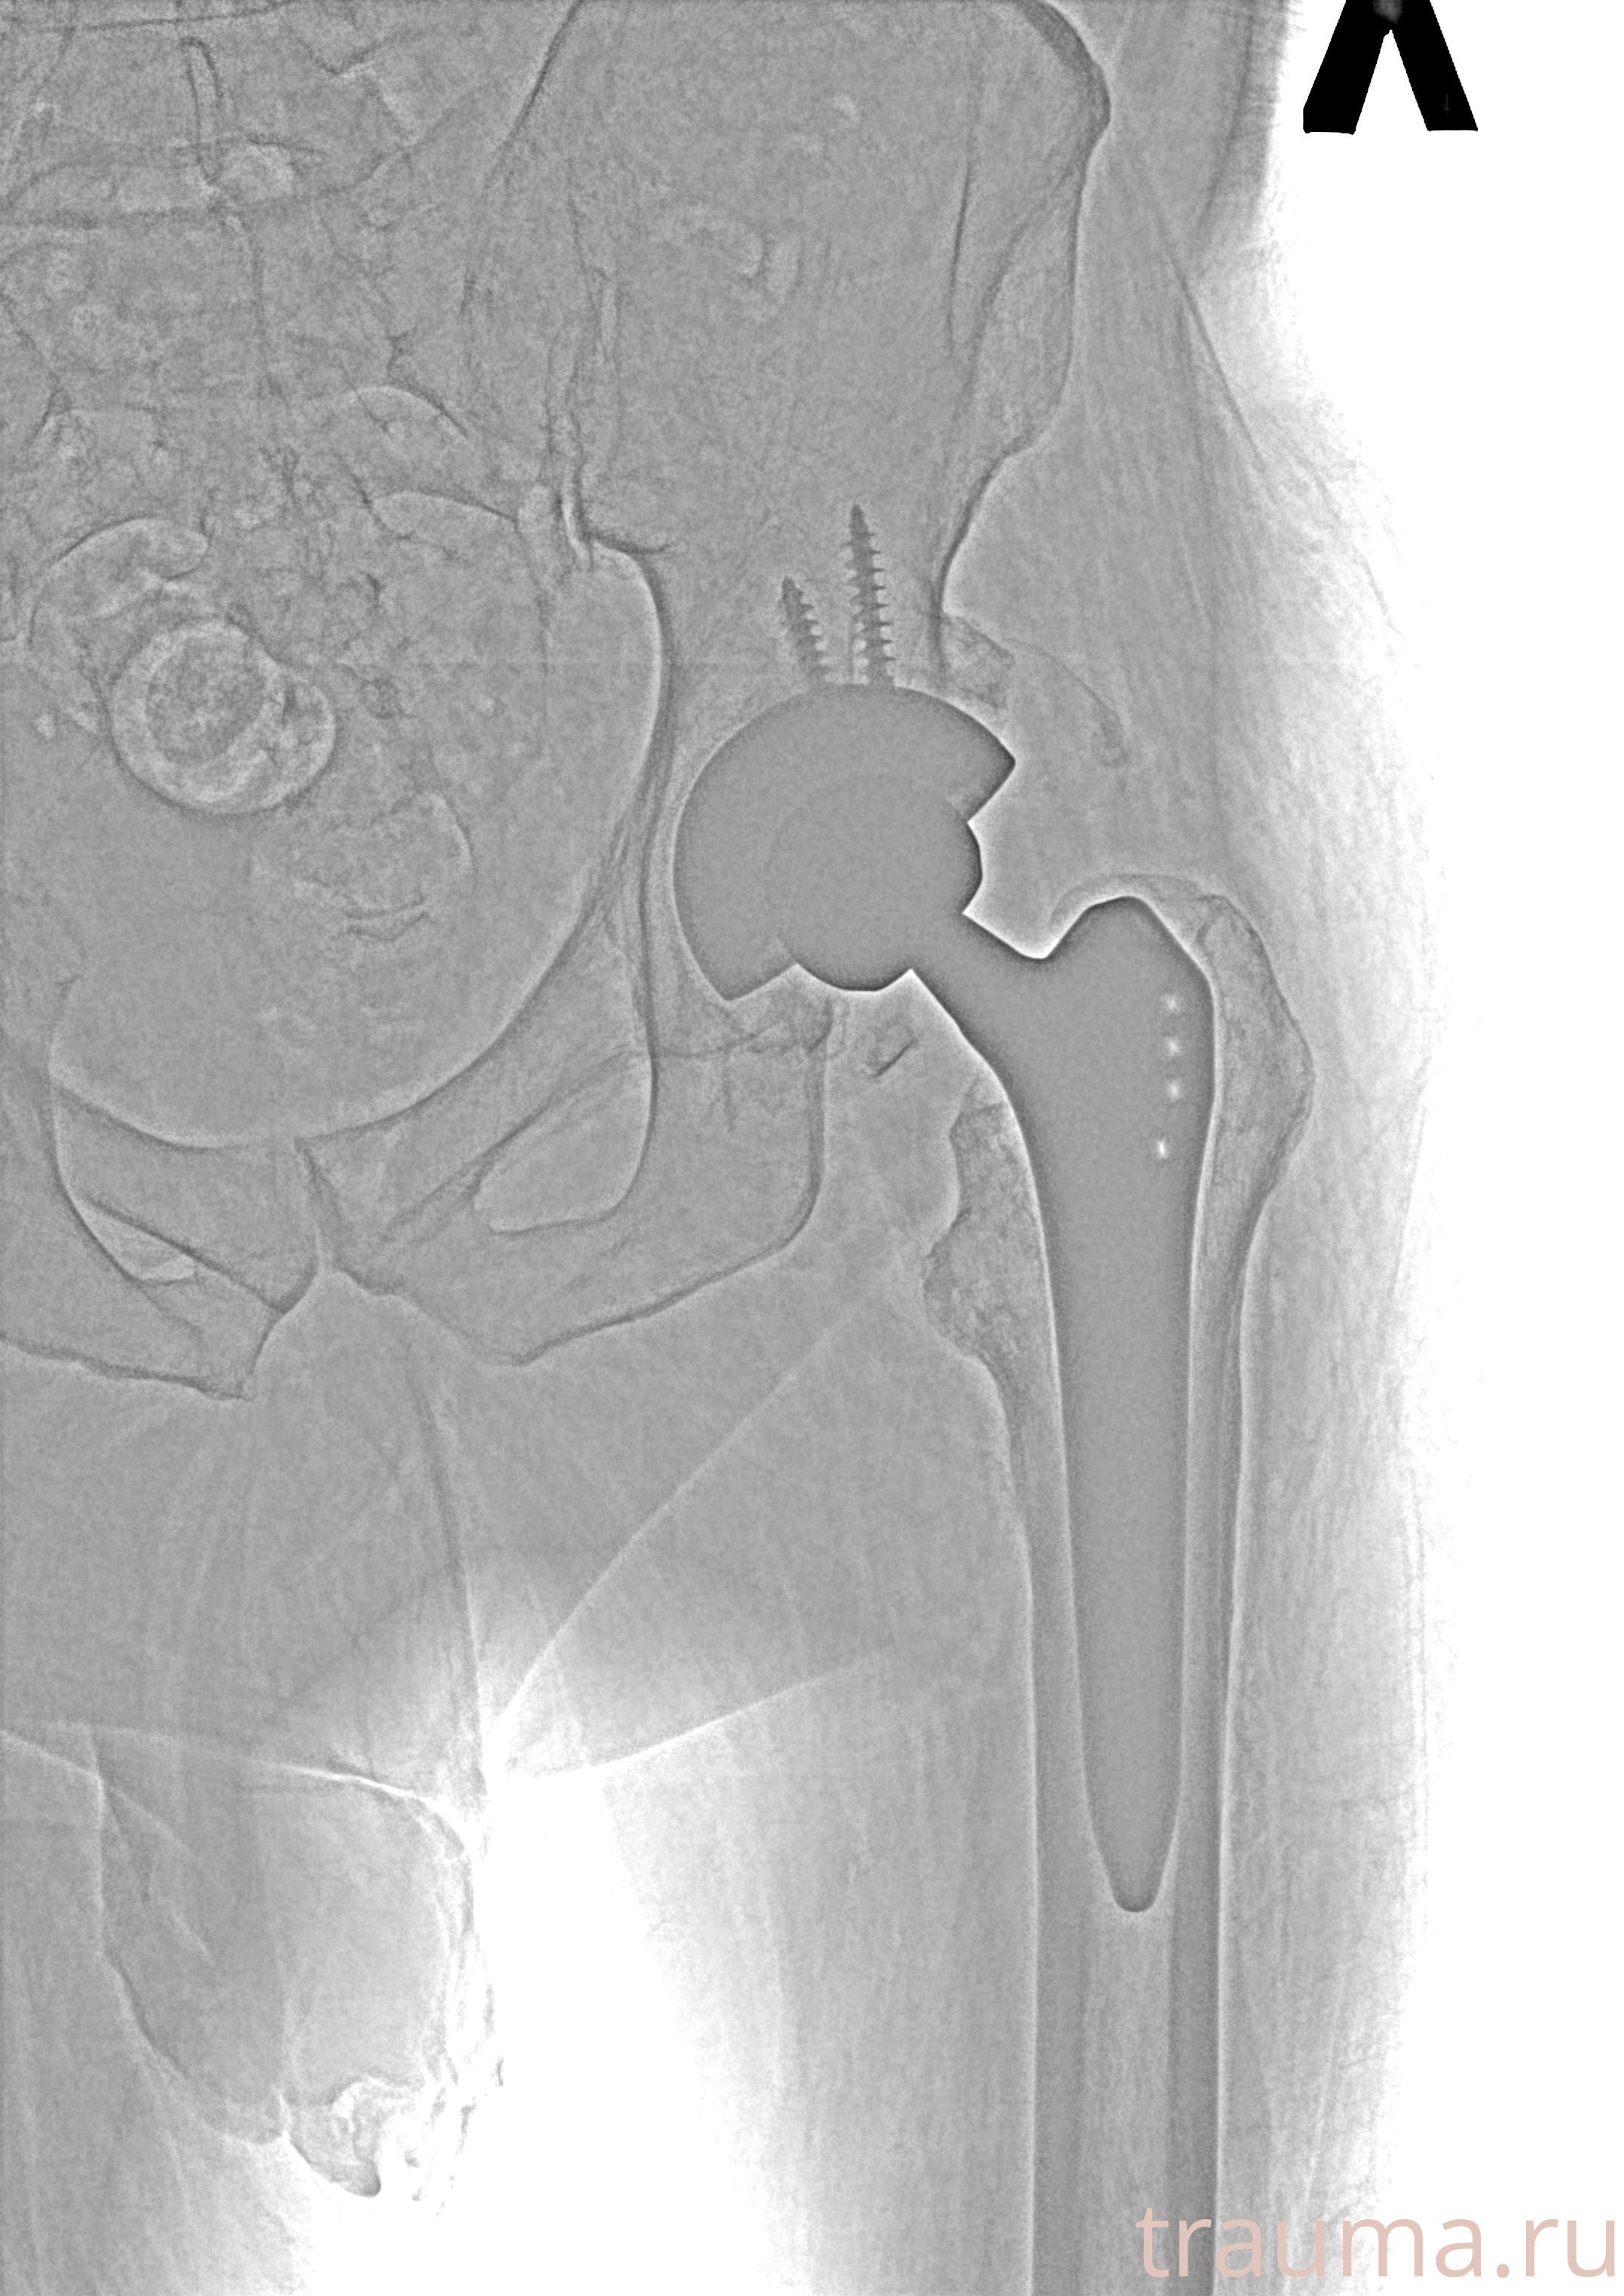

Рентгенограммы

Рентген на дому: по вашему адресу приезжает врач-рентгенолог, травматолог-ортопед с мобильным рентгеновским аппаратом, проводит диагностику травмы или заболевания, делает необходимые рентгенограммы, дает рекомендации по дальнейшему лечению. Получить качественные снимки в домашних условиях возможно благодаря уникальной методике, разработанной МосРентген Центром для института  Склифосовского